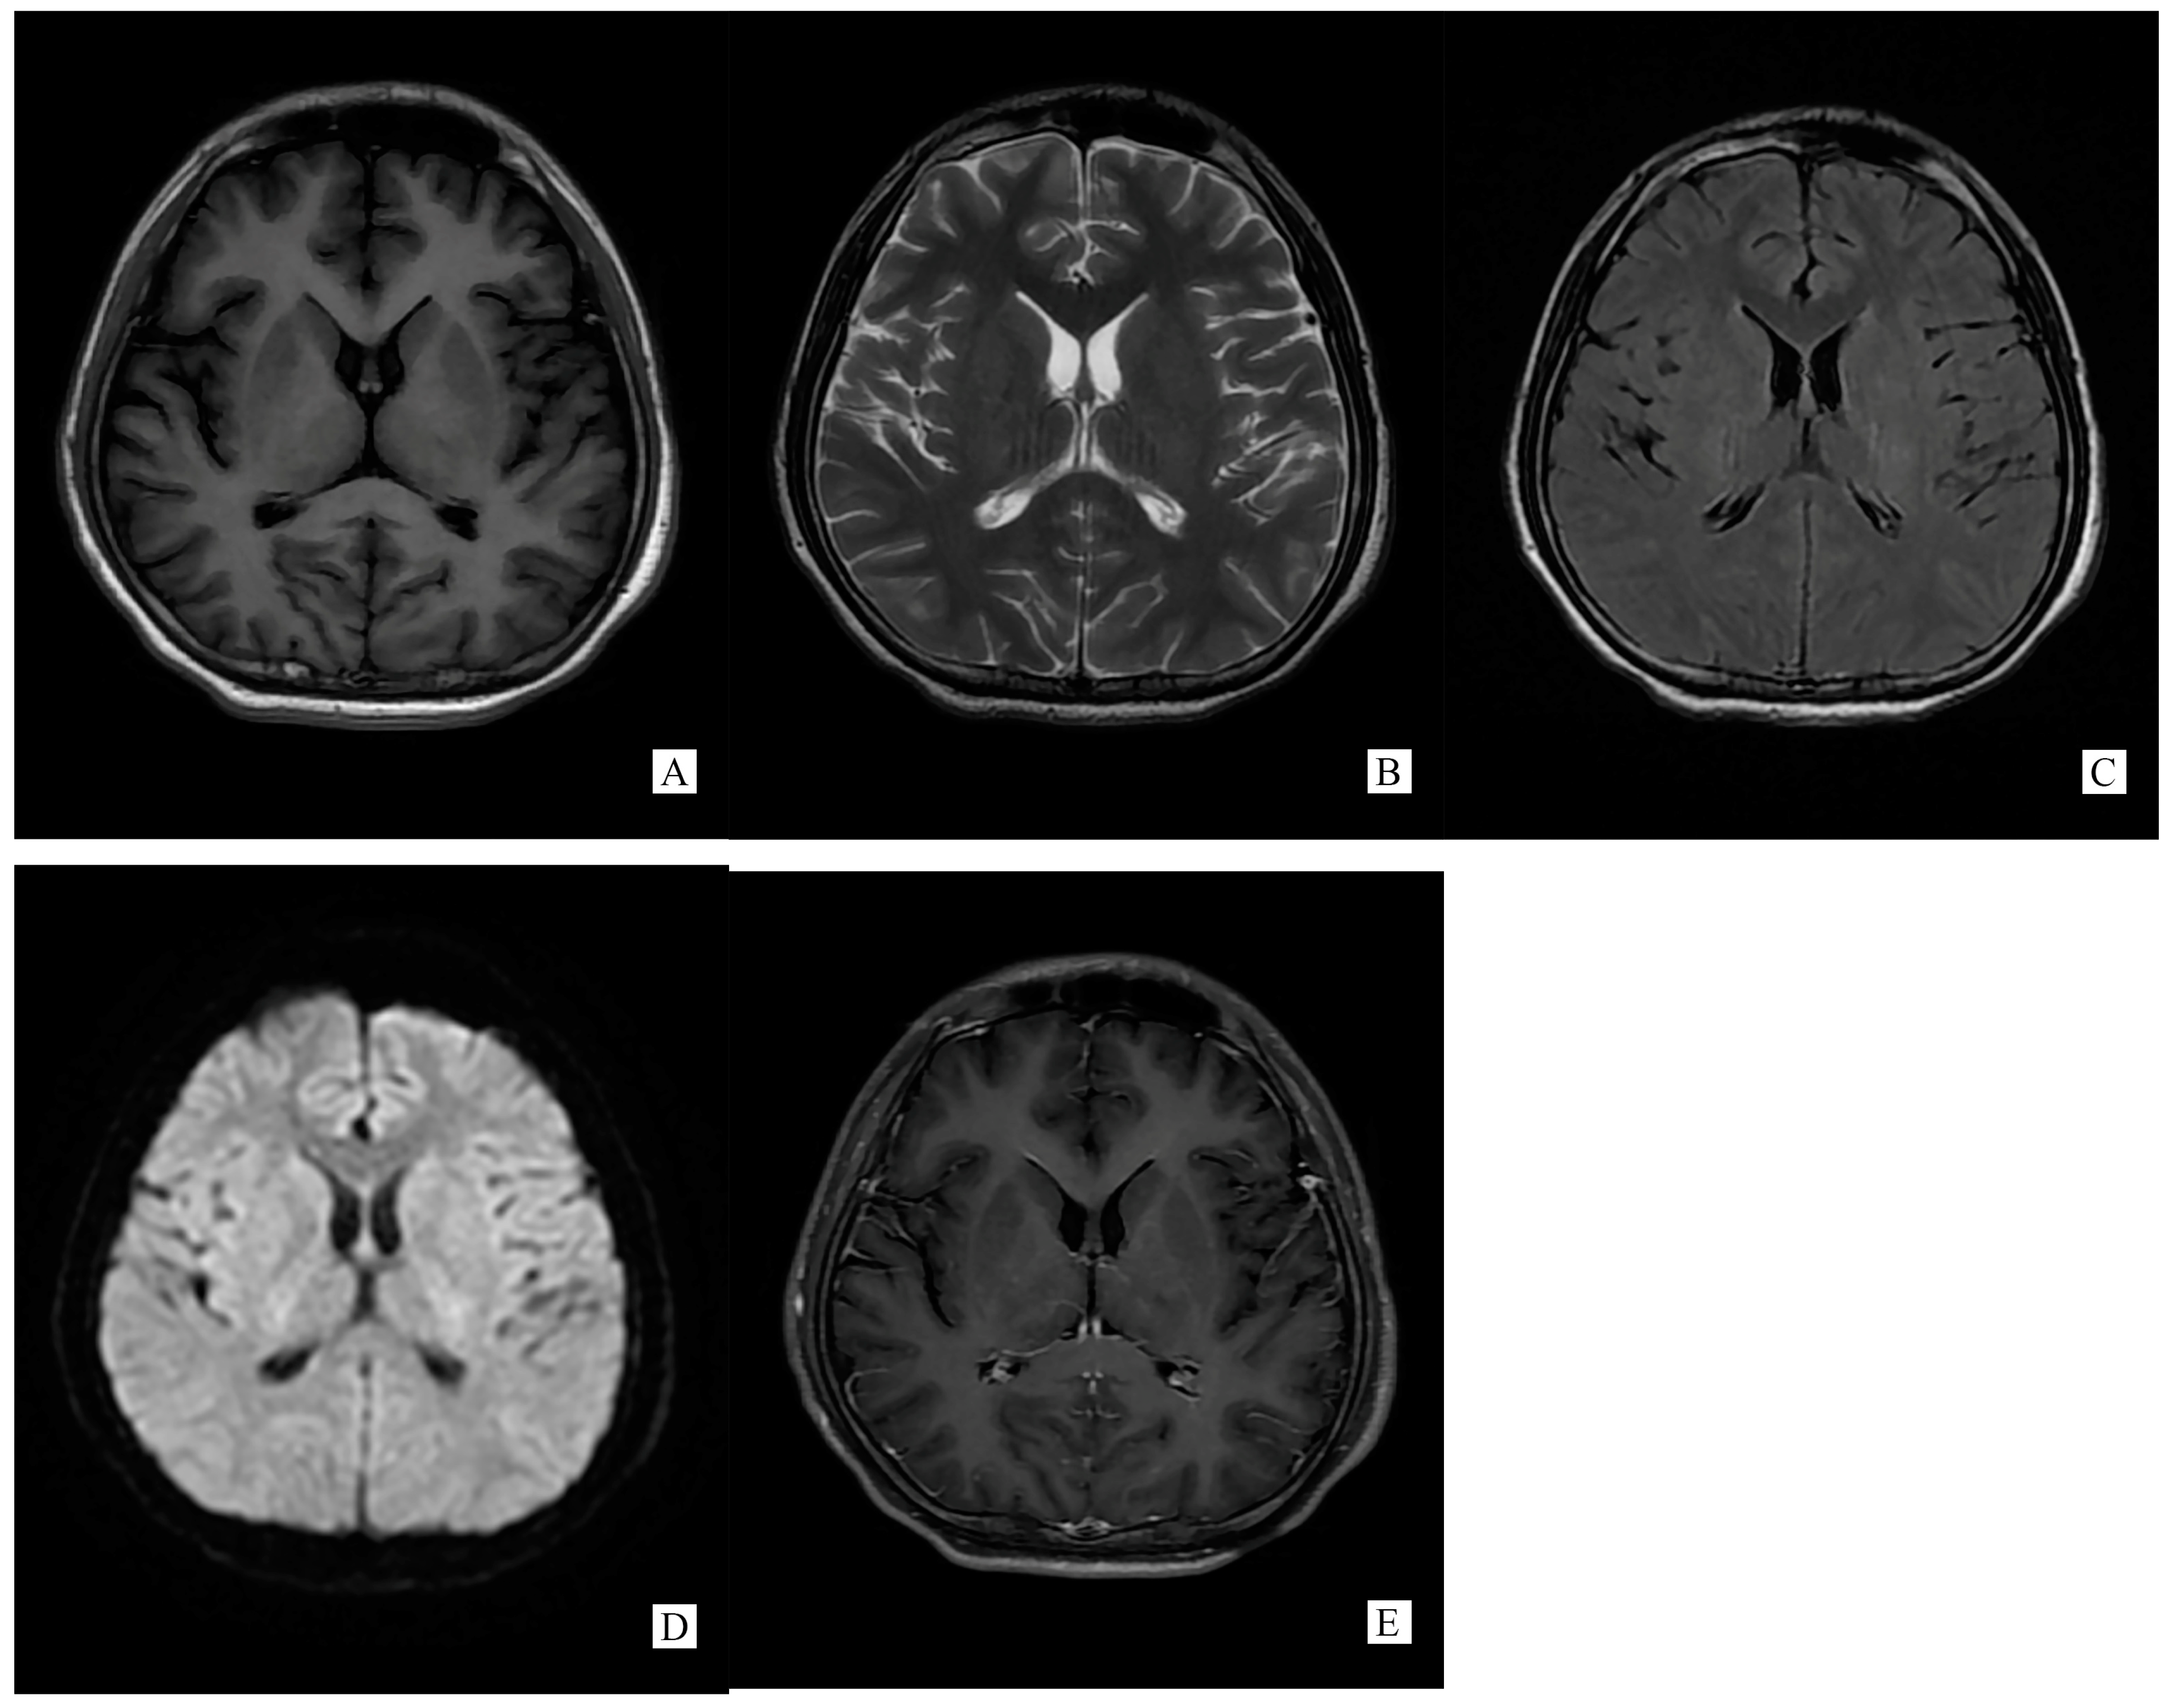

Figure 2.

(Performed on 13 November 2021) SCC lesion totally disappeared on brain MRI ((A). T1WI, (B). T2WI, (C). T2 flair, (D). DWI, (E). Post-gadolinium T1-weighted).

A repeated spinal tap was performed on 11 November 2021, which showed increased intracranial pressure, CSF glucose was still below normal contents, while CSF protein and chloride was lower than before and still abnormal (ICP 330 mmH2O, Glu 2.14 mmol/L, Cl− 119.50 mmol/L, Pro 1.05 g/L). WBC counts increased to 500 × 106/L. CSF screen using next-generation sequencing (NGS) indicated no infection. The CSF test of neural auto-antibodies revealed positive anti-GFAP antibodies (antibody titer 1:32), while the serum test was negative. CSF Ig electrophoresis revealed positive IgG oligoclonal bands (≥2 bands). A second cerebral MRI was performed on 13 November 2021 showing totally disappeared on SCC lesion (Figure 2).

Generally, typical features of autoimmune GFAP astrocytopathy present as a linear, radial perivascular enhancement pattern on brain MRI, and central longitudinally extensive enhancement pattern on spinal cord MRI [7]. RESLES is typically classified into two patterns on MRI: type I is an isolated lesion on SCC, type II is a lesion in SCC expending to callosal fibers, cerebral white matters or anterior portion of corpus callosum. No matter type I or type II, lesions can be significantly shrunk or totally disappeared within a month, accompanied with the relief of symptoms [8]. In the MRI of our case, the lesion was located in the SCC, manifested a hypointense signal on T1WI and hyperintense on T2WI and DWI, reversibly, which is similar to type I RESLES, but unlike the typical autoimmune GFAP astrocytopathy.